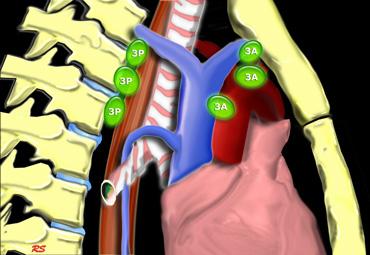

3A.Trước mạch máu

Các hạch này không tiếp giáp với khí quản như các hạch ở nhóm 2, mà nằm ở phía trước các mạch máu.

3P.Trước cột sống

Các hạch không tiếp giáp với khí quản như các hạch ở nhóm 2, mà nằm sau thực quản, tức là ở vị trí trước cột sống.

3. Hạch trước mạch máu và trước cột sống

Hạch nhóm 3 không nằm kề khí quản như hạch nhóm 2.

Chúng có thể là:

3A nằm phía trước các mạch máu, hoặc

3B nằm phía sau thực quản, vốn nằm ở vị trí trước cột sống.

Hạch nhóm 3 không thể tiếp cận bằng nội soi trung thất.

Hạch 3P có thể tiếp cận bằng siêu âm nội soi (EUS).

Bên trái là hạch 3A nằm trong khoang trước mạch máu.

Lưu ý cũng có các hạch cạnh khí quản dưới bên phải, tức là hạch nhóm 4R.